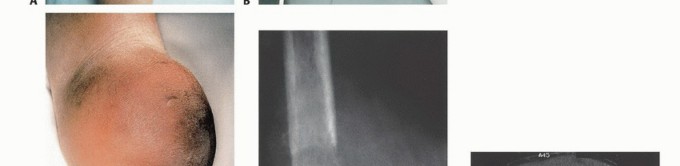

- الكتلة أو التورم: ظهور كتلة غير طبيعية أو تورم في الفخذ، قد تكون صلبة أو مؤلمة عند اللمس، وتزداد حجمًا بمرور الوقت.

- تغيرات في الجلد: تقرحات جلدية، تغير في لون الجلد، أو التهابات متكررة فوق منطقة الورم.

- الأشعة السينية (Plain Radiography): غالبًا ما توفر الأشعة السينية أول إشارة للحاجة إلى البتر وتقدير مبدئي لمستوى البتر المطلوب. يمكن أن تكون الصور العرضية لعظم الفخذ والساق مفيدة في إظهار انتشار الورم ومدى تدمير العظام. ومع ذلك، قد لا تظهر النتائج الإشعاعية إلا بعد تدمير ما يصل إلى 30% من بنية العظم.